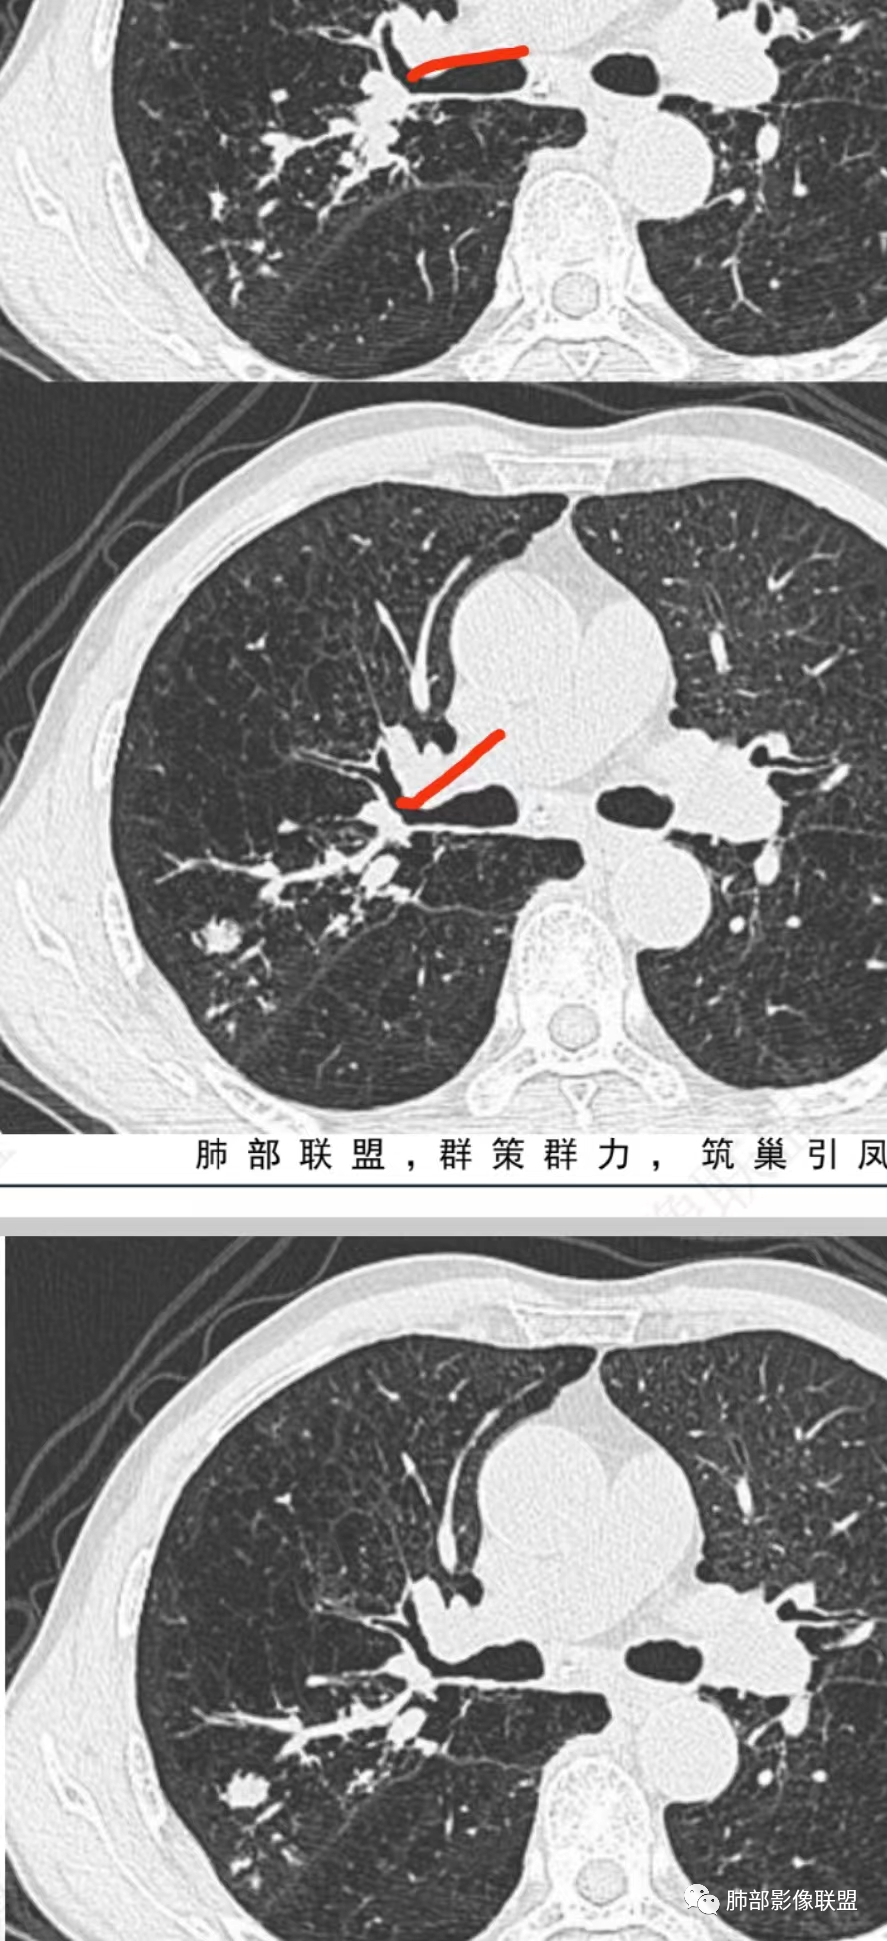

1、支气管粘液栓的表现∶多位于肺门的外侧,紧邻肺门,少数位于肺野外周,走行与正常支气管走行类似,而原来相对应区域的支气管缺失或阻塞。呈分支状或指套状结构,近端闭锁,不与支气管相通,与CT扫描层面平行时为"V"形、"Y"形或多个分支条状,与CT层面垂直时为类圆形结节状,MSCT应用MPR可行任意角度重组观察黏液栓的形态及其与近端支气管、血管的关系。黏液栓多为水样密度或软组织密度(较粘稠的黏液).但增强扫描无强化;内可有气体影,形成液气平面。伴随肺动脉细小。

2、间接征象∶周围肺气肿或阻塞性炎性改变。绝大部分都伴随不同程度的肺气肿,常见的是较大面积的肺气肿,其内血管比较纤细,也有报道可以不伴随肺气肿,但是罕见。

柱状支气管扩张-轨道征(柱状支扩)。增厚的支气管壁与扩张中空的支气管类似于轨道,边缘比较光滑肺部像聪驱远端稍增宽或等宽,走形较自然、顺畅。增厚的支气管壁类似于铁轨,见于柱状扩张。腔内有粘液栓时要与血管鉴别。

静脉曲张样扩张∶ 主要是支气管壁破坏更明显,边缘凹凸不平,各段扩张的程度不一,支气管呈曲张的静脉一样或串珠状。是柱状扩张向囊状扩张过渡的一个阶段,是牵拉性支气管扩张常常会表现的一种形式。

支气管扩张--粘液栓。

支气管扩张--树芽征。树芽征∶指CT表现为靠近胸膜下区小叶中心直径为3~5 mm的分支部影像联附状线影和与其相连的细支气管横断面结节影,状如春天里树上挂满树芽,即树芽征。是细支气管扩张、阻塞的特征影像之一。树芽征不是一个病,而是一组疾病可能出现的CT征象,胸部X线片不能发现如此细小的病变。